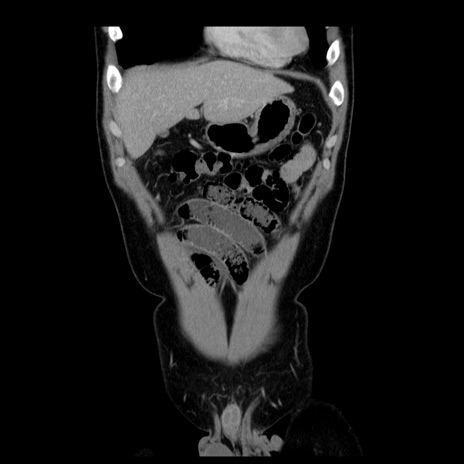

症例4(冠状断像)

【症例】30歳代男性

【主訴】腹痛、嘔吐

【現病歴】昨晩から突然の腹痛あり、その後嘔吐、軟便も出現。腹痛が改善しないため救急搬送となる。2日前にしめ鯖の食事歴あり。

【身体所見】意識清明、苦悶様、BP 135/90mmHg、BT 35.7℃、腹部:平坦、やや硬、心窩部〜臍部に自発痛、圧痛あり、筋性防御+、反跳痛-

【データ】WBC 8100、CRP 0.57